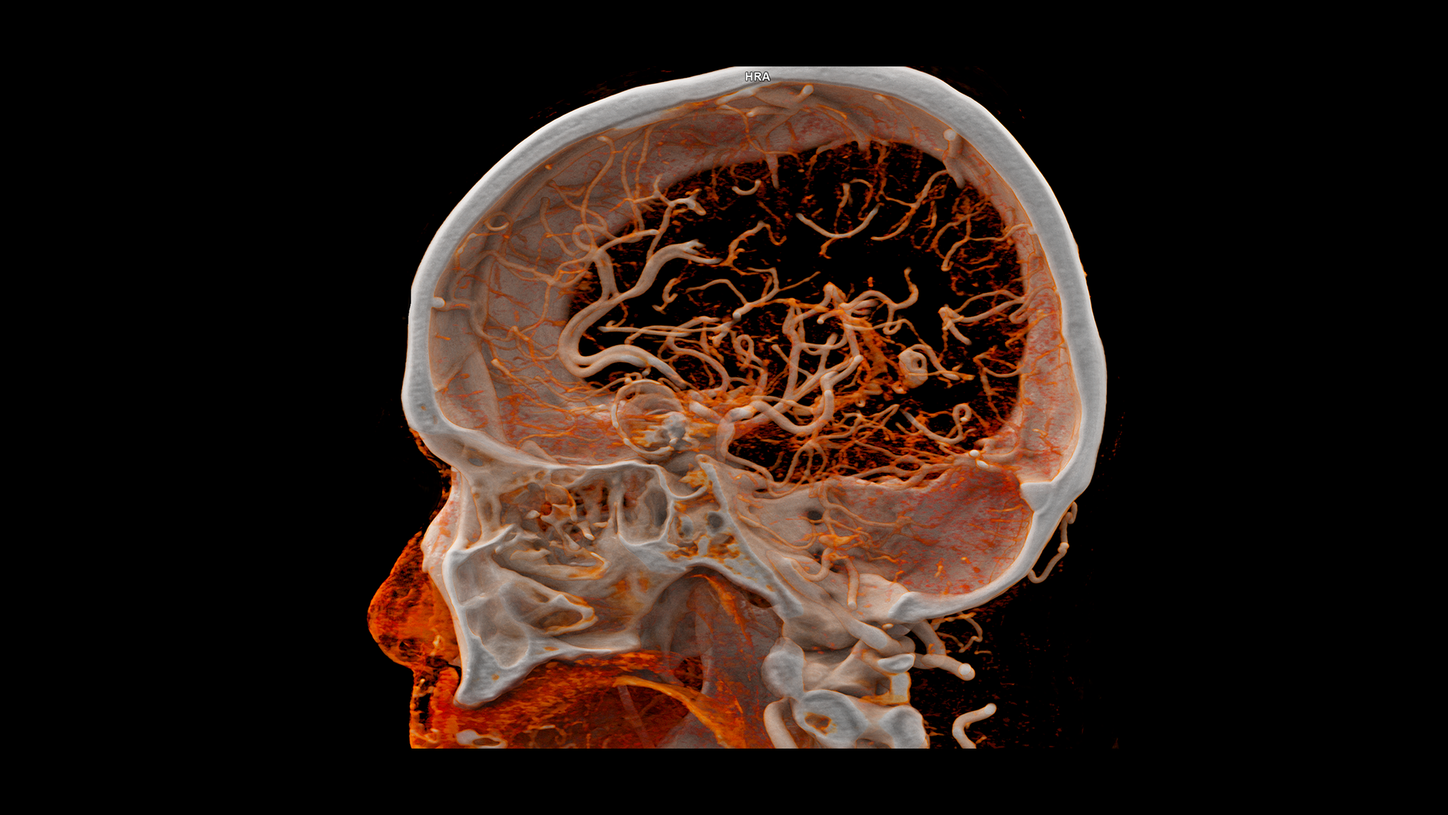

At the heart of NAEOTOM Alpha® is a radically new photon-counting detector. The QuantaMax detector directly converts X-rays into an electrical signal, which is then used to create an image. The energy of each X-ray is measured, so spectral information is available for every scan, and the images are contrast-rich with high spatial resolution at the same dose. Combining the high spatial resolution of the QuantaMax photon-counting detector with our Dual Source temporal resolution enables the visualization of fine details for increased diagnostic confidence.